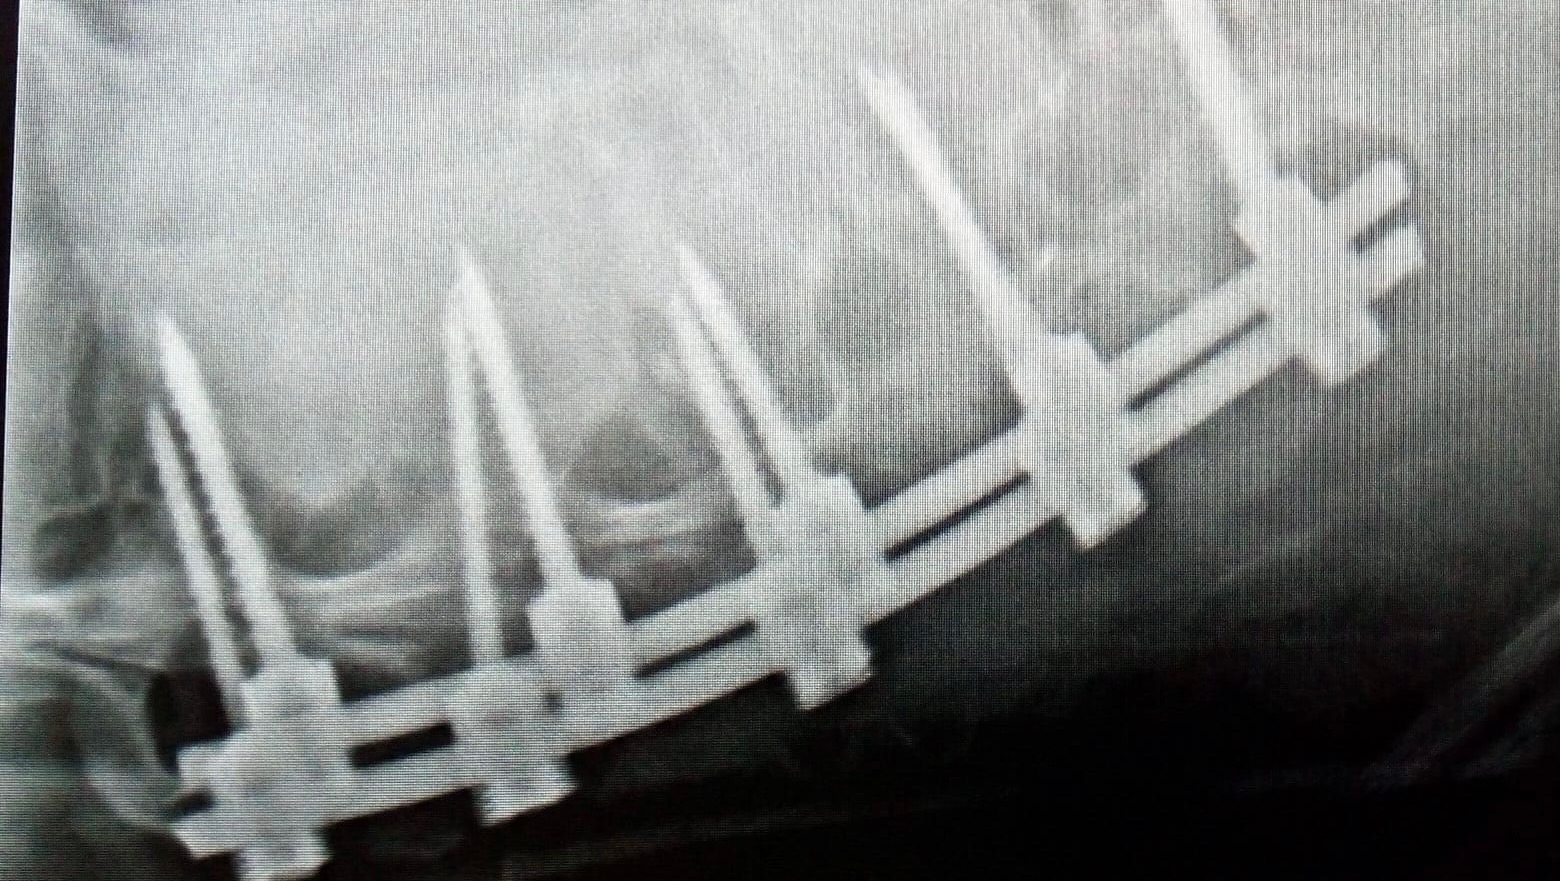

severe fall, down a flight of stairs in her home on 7/8/22. She crushed her L1 vertebrae upon

surgery on 7/9/22. My mom’s lower lumbar vertebrae L1-L5 were fused together to stabilize her

spine and release nerve compression. She has been in the hospital for 6 days and is being